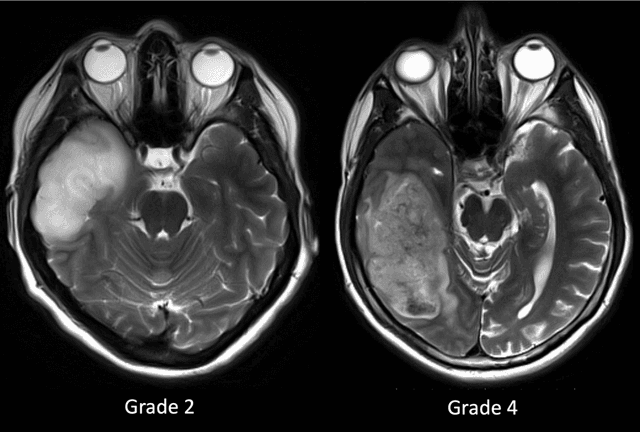

Purpose; The purpose of this study is to classify glial tumors into grade II, III and IV categories noninvasively by application of machine learning to multi-modal MRI features in comparison with volumetric analysis. Methods; We retrospectively studied 57 glioma patients with pre and postcontrast T1 weighted, T2 weighted, FLAIR images, and ADC maps acquired on a 3T MRI. The tumors were segmented into enhancing and nonenhancing portions, tumor necrosis, cyst and edema using semiautomated segmentation of ITK-SNAP open source tool. We measured total tumor volume, enhancing-nonenhancing tumor, edema, necrosis volume and the ratios to the total tumor volume. Training of a support vector machine (SVM) classifier and artificial neural network (ANN) was performed with labeled data designed to answer the question of interest. Specificity, sensitivity, and AUC of the predictions were computed by means of ROC analysis. Differences in continuous measures between groups were assessed by using Kruskall Wallis, with post hoc Dunn correction for multiple comparisons. Results; When we compared the volume ratios between groups, there was statistically significant difference between grade IV and grade II-III glial tumors. Edema and tumor necrosis volume ratios for grade IV glial tumors were higher than that of grade II and III. Volumetric ratio analysis could not distinguish grade II and III tumors successfully. However, SVM and ANN correctly classified each group with accuracies up to 98% and 96%. Conclusion; Application of machine learning methods to MRI features can be used to classify brain tumors noninvasively and more readily in clinical settings.